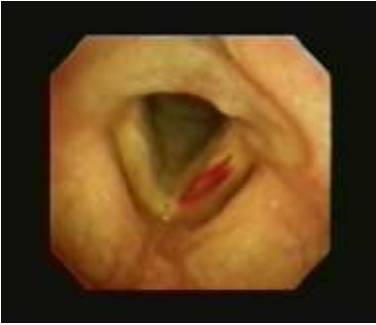

18 下图中所见异常的部位是:

A. 左声带

B.  右声带

C.  会厌

D. 勺状软骨

18A

这左侧声带的瘀斑是一次以可弯曲支气管镜通过声带进入气管的不成功尝试的结 果。会厌在这个图片中是不可见的。双侧声带都清晰可见,并且两者前联合(V的 端点),后联合(喉头宽的联合直观可见。杓状软骨 (这在图片中不可见的)是在这V 字宽底的两端。